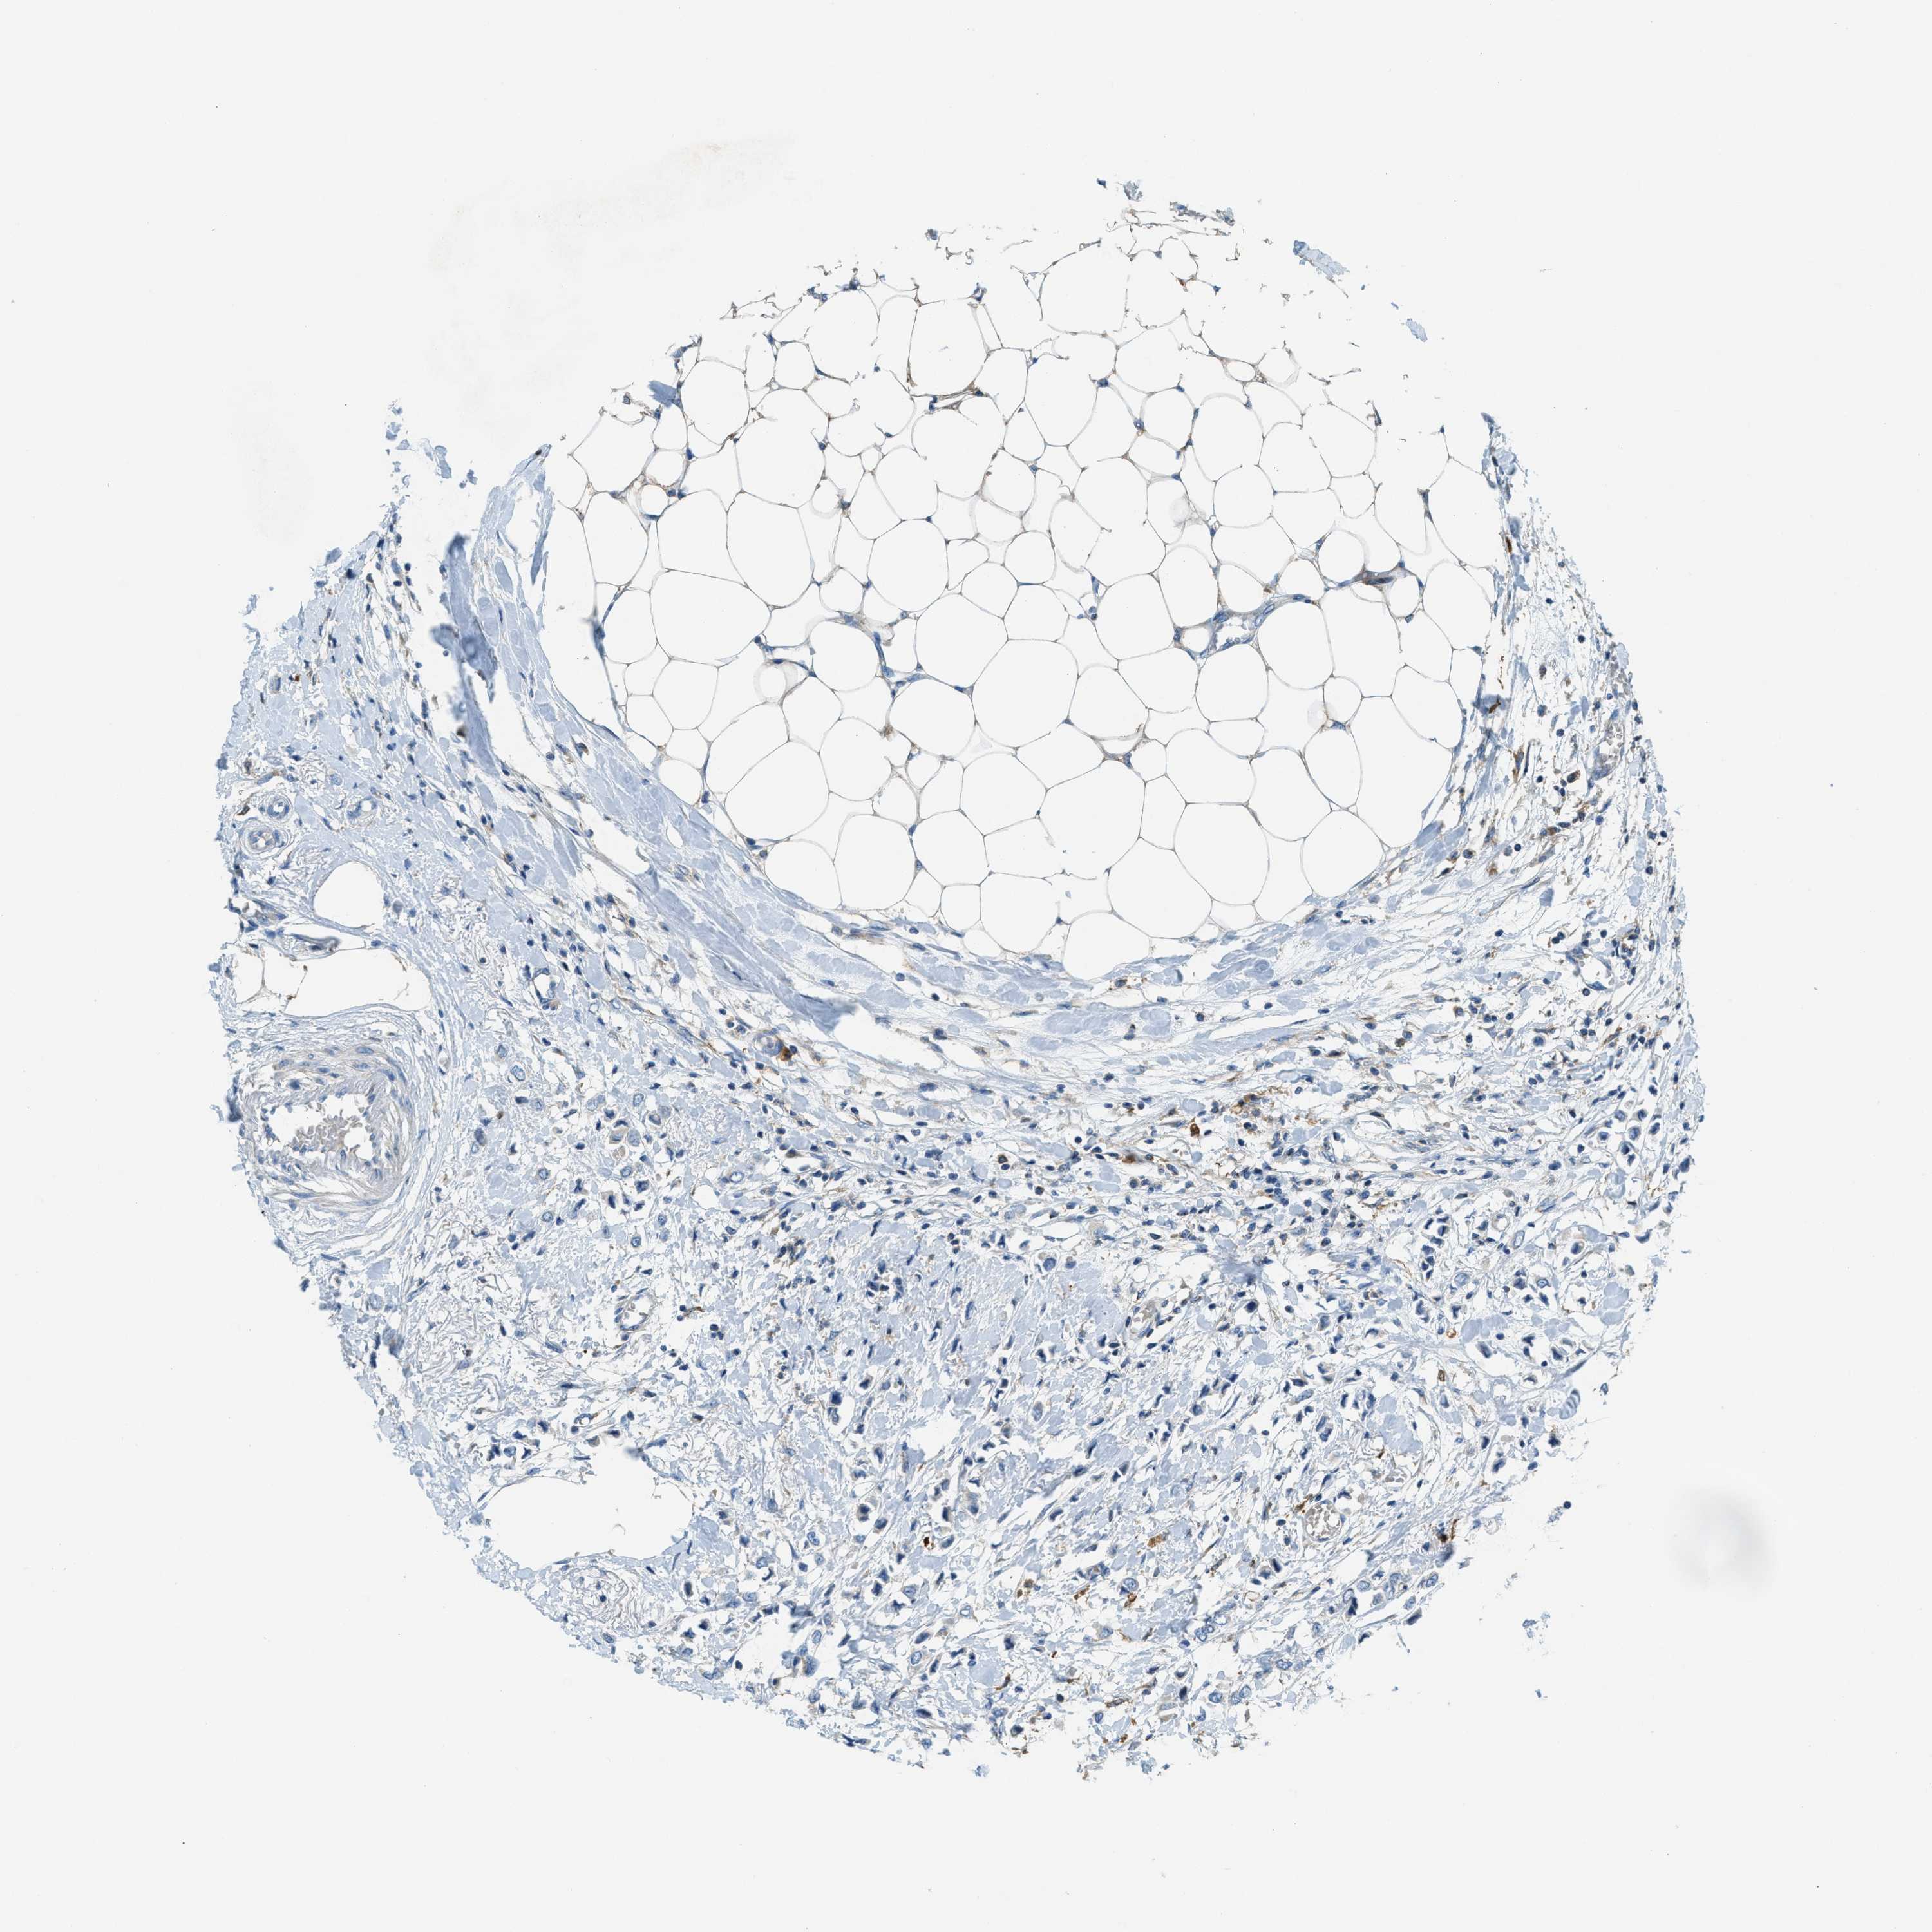

BRCA TCGA BRCA VALIDATION PROTEIN EXPRESSION

ANTIBODIES

AND

VALIDATION